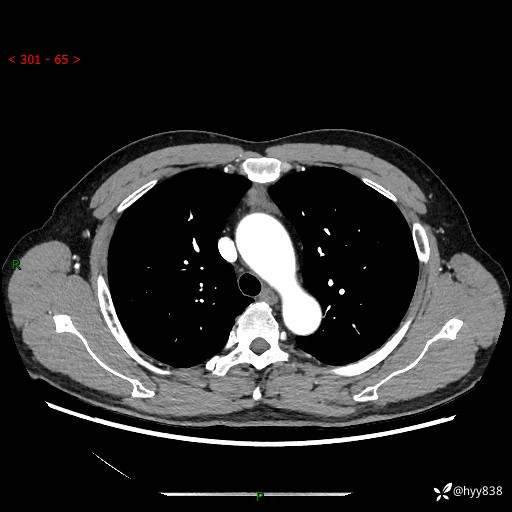

患者性别:女

患者年龄:49岁

简要病史:跟骨骨折,常规CT发现纵隔占位

辅助检查:CT

临床诊断:纵隔占位

增强(动脉期+静脉期)